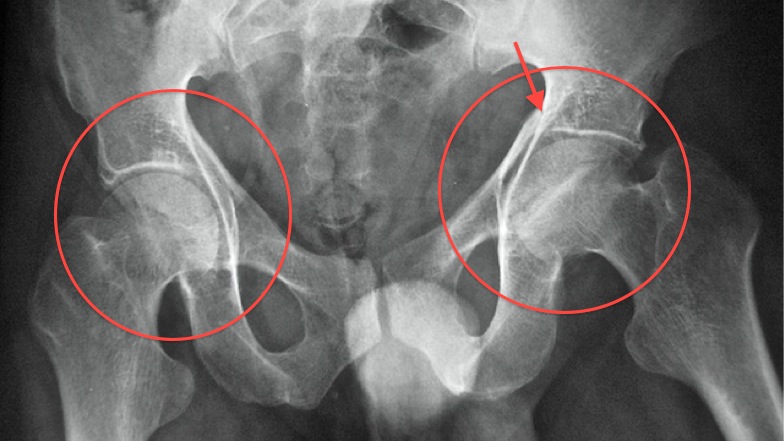

Рентгеновские снимки: Синовит тазобедренного сустава